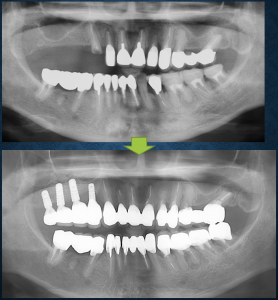

先日、フルマウスリコンストラクションのケースがようやく終わりました。患者さんは3年前に、なん件かの歯科医院を回られた後、当院にお越しになりました。主訴は「右上奥歯がなくなっているのをインプラントでやって欲しい」でした。レントゲンでは該当する部位にインプラントを埋入できるだけの骨がありませんでした。サイナスリフト(副鼻腔内造骨術)が必要でした。2002年に米国ミシガン大学で学んだこの技術には特別な思い入れがあります。骨が熟成するのに術後半年待ちますので、この処置を先に行い、インプラントを埋入する時期までの間に根管治療が必要な歯の治療などを行っていきました。

患者さんは仕事をされており、勤務先は大手町界隈ではなく電車で来られる方でした。治療開始から最初の1年は患者さんがなかなか時間が取れなくて進行は遅々としていました。サイナスリフトの手術の時は半日会社を休んで来られました。2年目から患者さんのスケジュールに余裕ができ治療が急速に進行しました。治療が終了した時は3年が経過していました。治療終了日には術前後の比較写真とレントゲンを患者さんにお渡ししました。ひずんだ咬合を完全に回復させることはできませんでしたが、私なりの答えを出せたのではないかと考えています。歯周病よりも咬合や歯根破折の要因で歯を失ってきた傾向にあると考え夜間のマウスピースも作成してお渡ししました。個々の歯で不安な要素もあり、今後の慎重な経過観察とトラブル発生時の早期対応が肝要です。